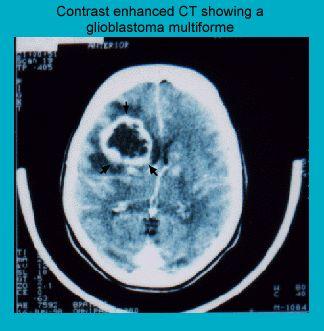

CT scan showing a glioblastoma multiforme